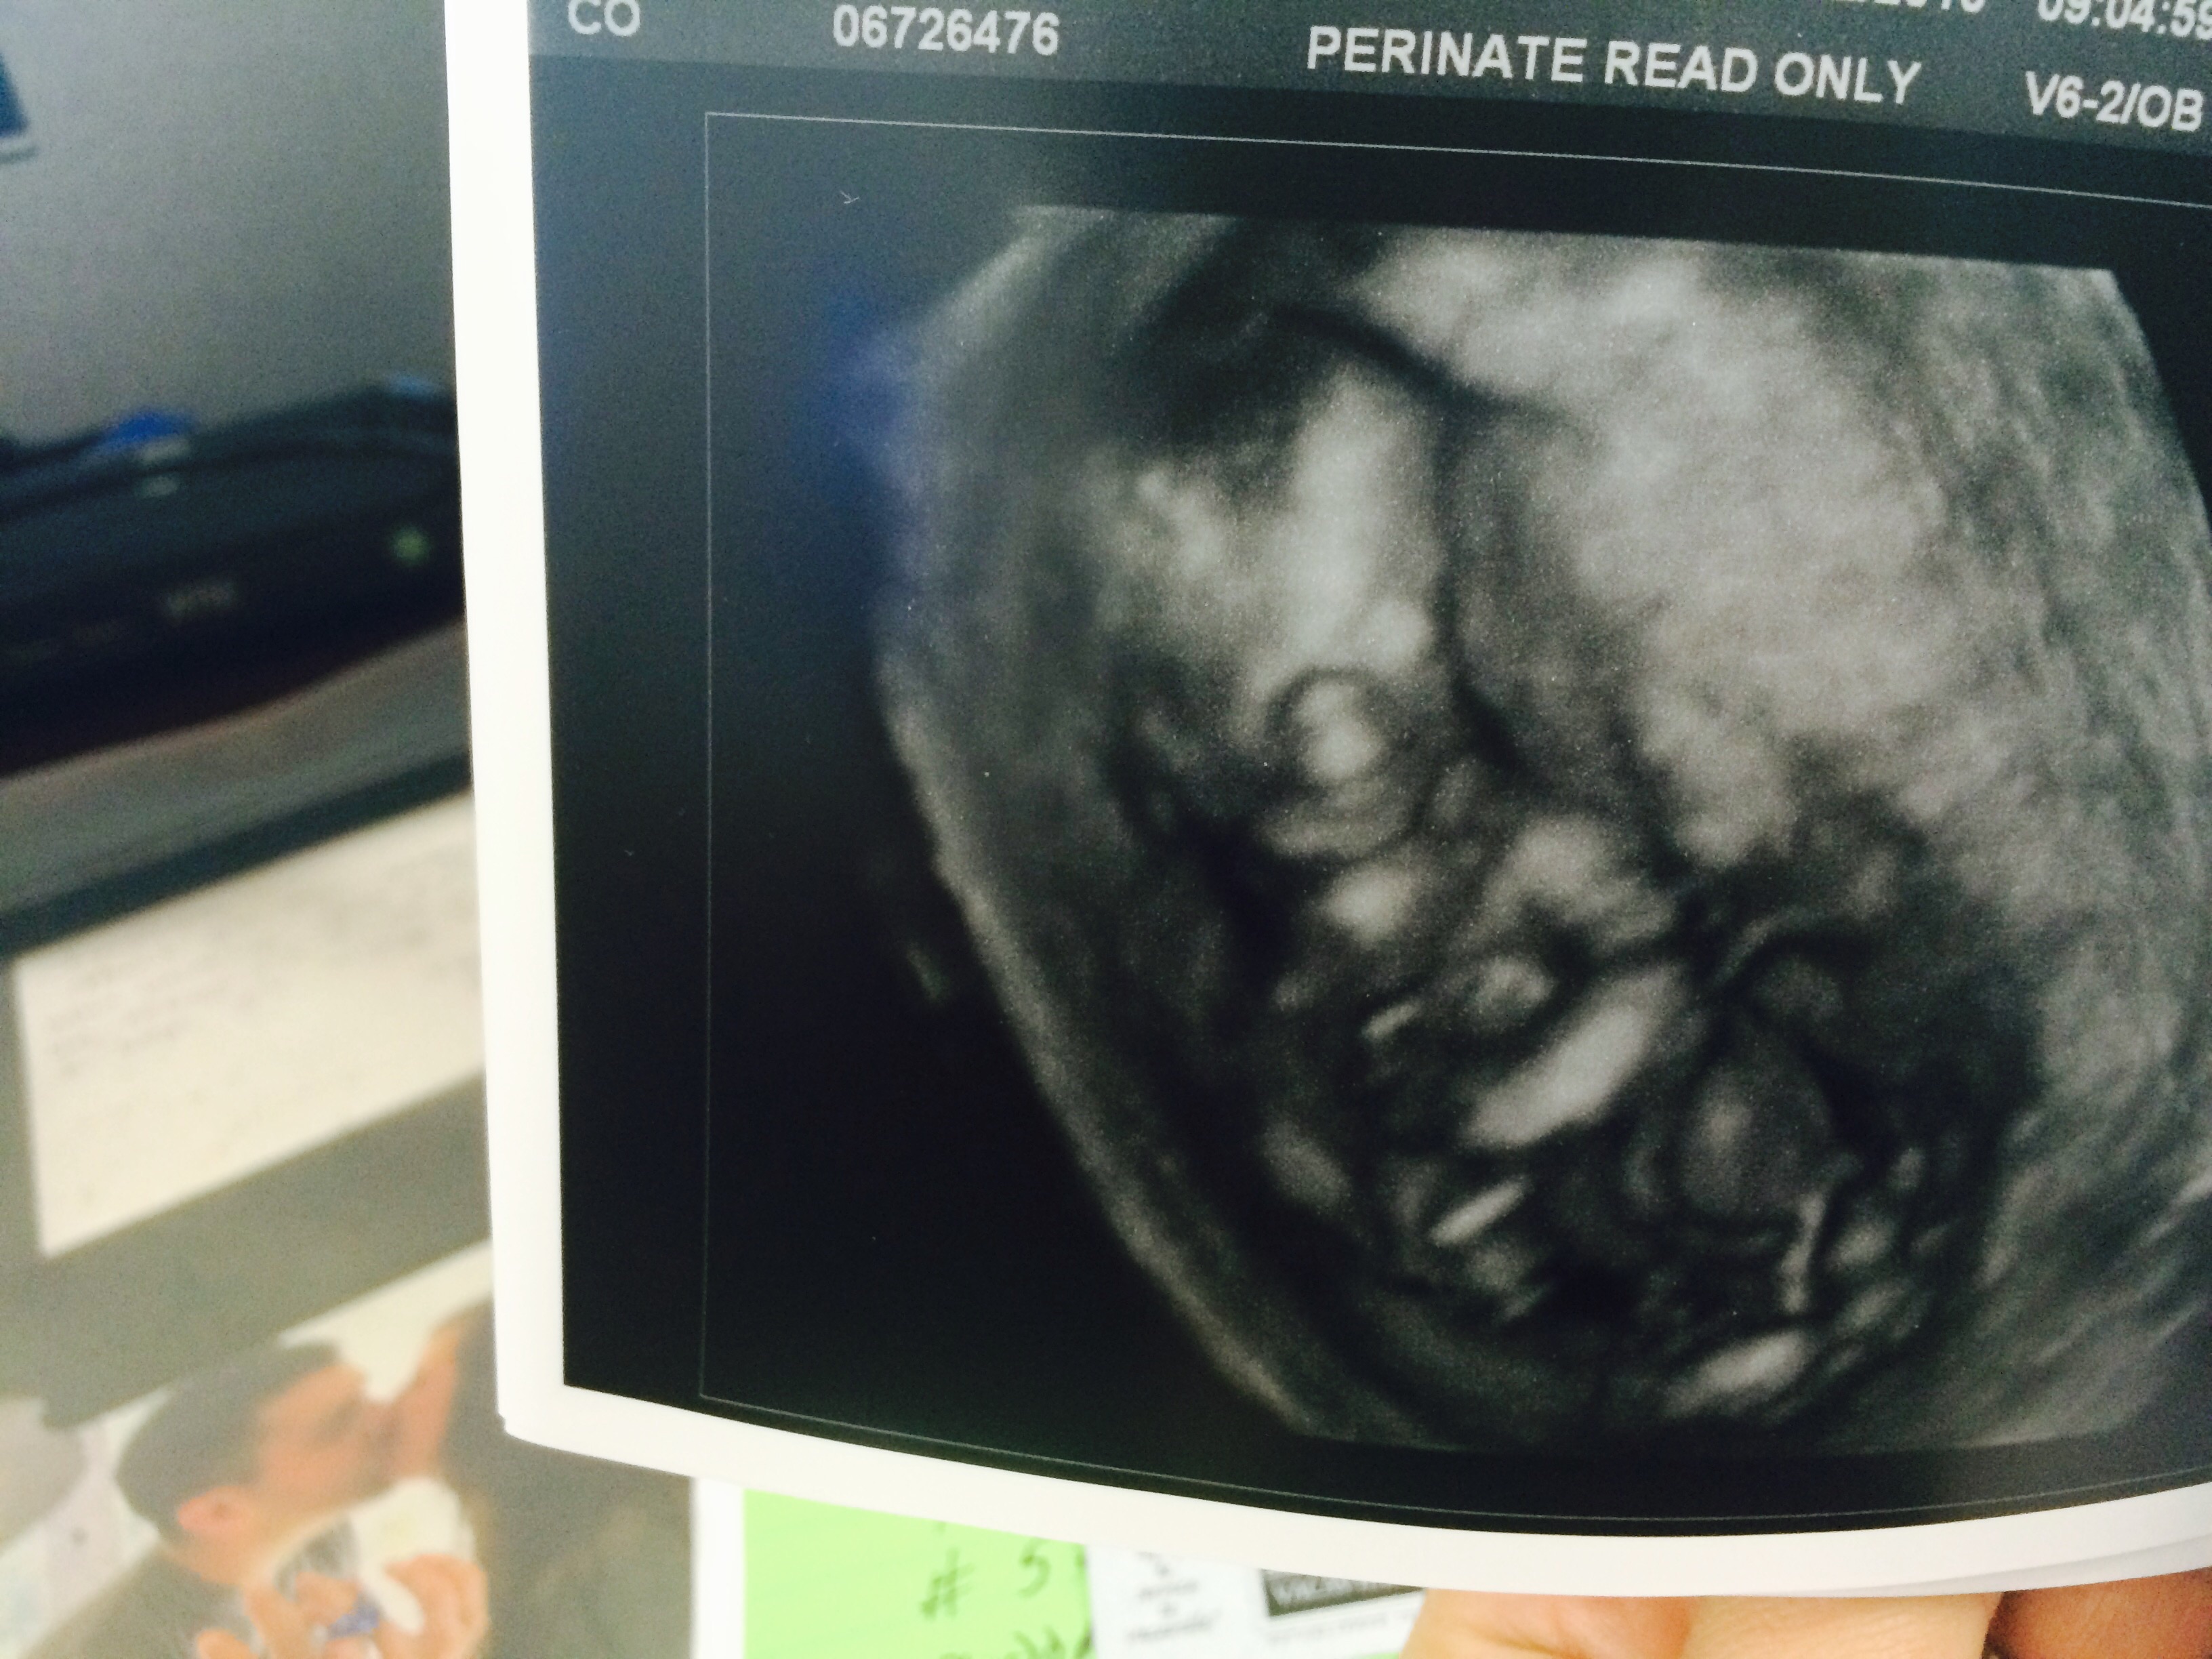

We had our second ultrasound last week when I was 11+3. Still measuring a bit bigger, she said I looked about 12 weeks during the scan. Everything looks healthy! Look at that little nose and lips!!!! So in love.